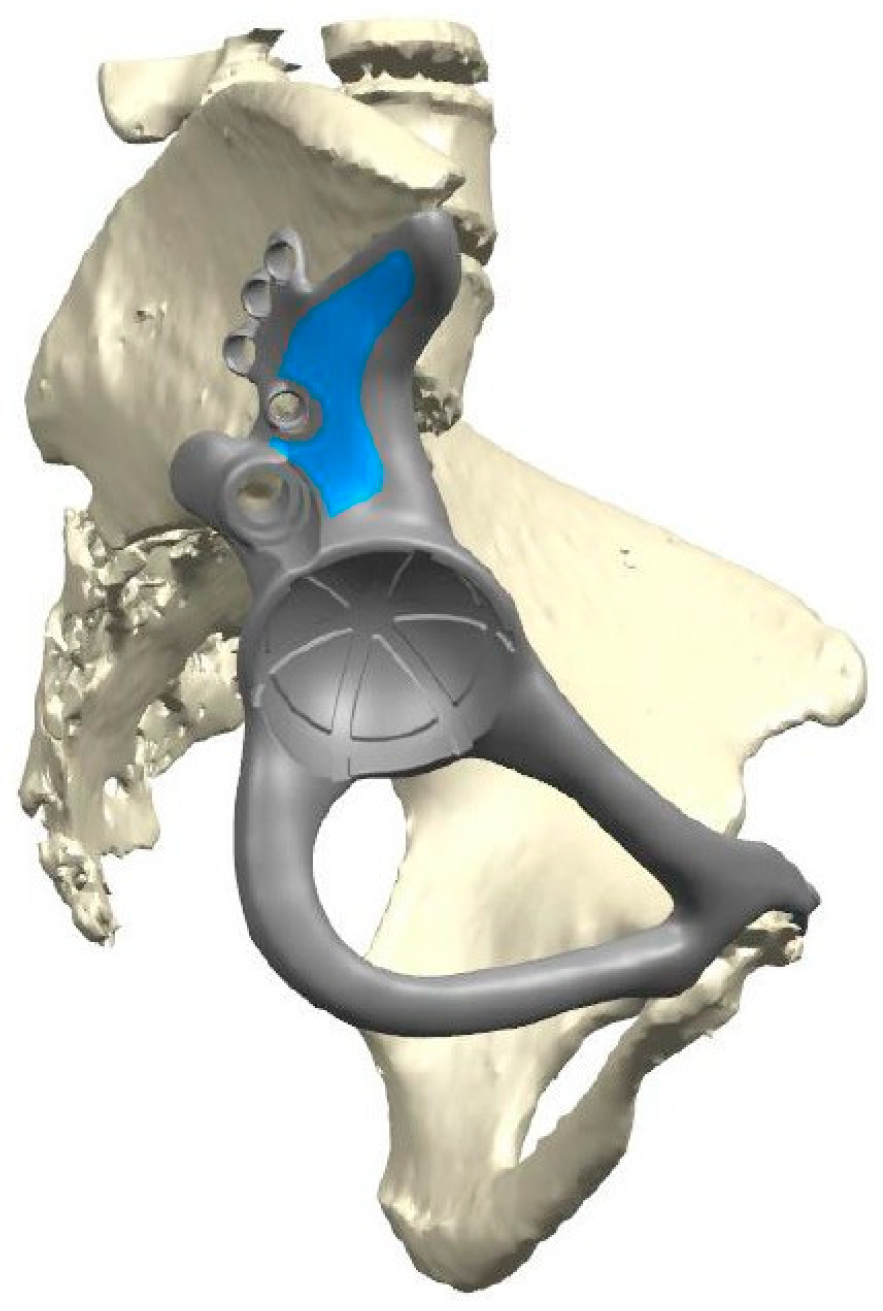

The same surgeon operated on all of the patients. The surgical procedure for custom partial pelvic replacement involves the precise removal of the tumor-affected bone parts, guided by patient-specific instrumentation according to precise pre-operative planning. The custom implant (Figure 3) is then secured using screws and a main stem, ensuring stability and functionality. In cases where the insertion of the main stem is challenging, an alternative fixation approach using cortical screws is employed. The overall goal is to successfully replace the affected portion of the pelvis while maintaining structural symmetry with the contra-lateral healthy side.

Figure 3. Positioned 3D-printed custom implant.